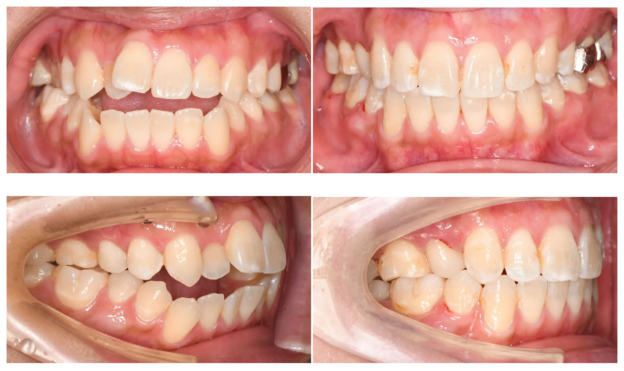

口腔内(正面)からは開咬と歯のねじれ、乱杭歯を確認

- 重度の開咬(オープンバイト)です。

- 上顎歯列弓の狭窄が著しいです。

- 強い叢生(ガタガタ歯、凸凹歯)が見られます。

口腔内(右側)からは口ゴボ、反対咬合を確認

- 上下前歯の強い唇側傾斜が見られます。

- 大臼歯は反対咬合(クロスバイト)となっています。

正面(口腔内)

開咬が完全に改善

上下の叢生も整い、理想的なアーチフォームに

右側

大臼歯の反対咬合が改善し、正常な咬合関係を獲得しました。